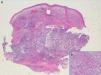

Additional tests included skin ultrasound with a linear 18MHz probe (Esaote MylabGold 25), which revealed a well-defined, hypoechoic subepidermal structure measuring 3.29×1.14cm. This area was continuous with an irregular, heterogeneous hypoechoic area that formed tracts that extended into a destructured hypodermis. Color Doppler showed increased local vascularity. Other additional tests included a complete blood count, which showed no evidence of infection, cultures, which were negative, and a skin biopsy from one of the lesions, which revealed an abundant neutrophilic inflammatory infiltrate in the dermis and that extended into the subcutaneous cellular tissue, as well as foci of abscess formation in the dermis, dissecting through the tissue (Fig. 3). Based on these findings, we made a diagnosis of chronic myeloproliferative syndrome-associated pyoderma gangrenosum (PG) and started treatment with oral prednisone at a dose of 1mg/kg/d.